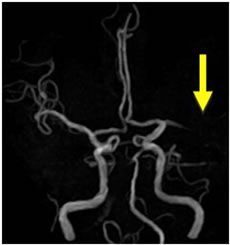

当院で行われた血栓除去術の実際の症例をお示しします。1例目は65歳男性、自宅にて動けなくなっているところを発見されました。軽度意識障害、重度の左片麻痺にて当院に救急搬送、NIHSS17点、心房細動を認めました。頭部MRI(図4)にて右大脳半球に矢印のように虚血巣の出現あり、MRA(図5)にて矢印のように右中大脳動脈の描出なく、緊急にて血管撮影を施行しました。バルーン付きのガイディングカテーテルを入れて、血栓より遠位にマイクロカテーテルを入れて、血栓の遠位からステント(Trevo provue 4×20mm)を展開後、血栓を回収しました。その後の撮影では閉塞していた血管はTICI2bまで再開通しており、治療直後から患者さんの左片麻痺は改善を認め、翌日のMRIでも梗塞巣は広範とならず、治療17日後に自宅退院しました。現在は社会復帰しており、元のお仕事にも戻っております。(図6、7、8、9参照)

図4:MRI拡散強調画像 |

図5:MRAで左内頚動脈描出なし |